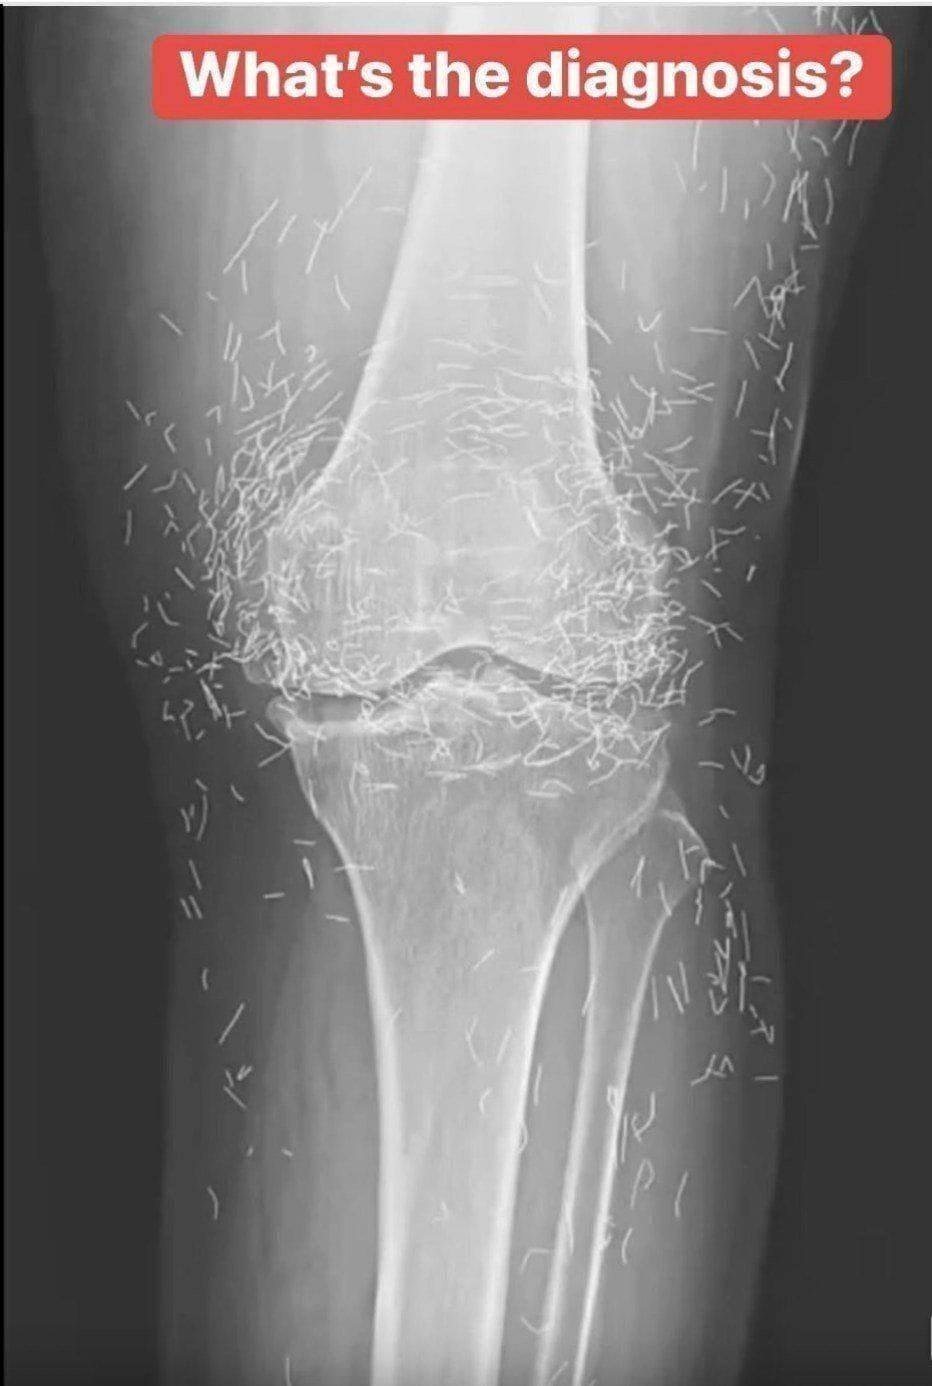

Years later, when doctors took X-rays to evaluate her knee condition, they weren’t prepared for what appeared on the images. Her knees were filled with dozens of bright, metallic flecks — tiny needles embedded deep within the joint area.

The findings were later documented in a case published by the New England Journal of Medicine.

In her case, the needles — believed to be made of gold — were intentionally left inside her knees.

Beyond inflammation, the needles created another problem: imaging complications. Metal objects can obscure parts of the anatomy on X-rays, making it harder for doctors to clearly assess joint damage or disease progression.